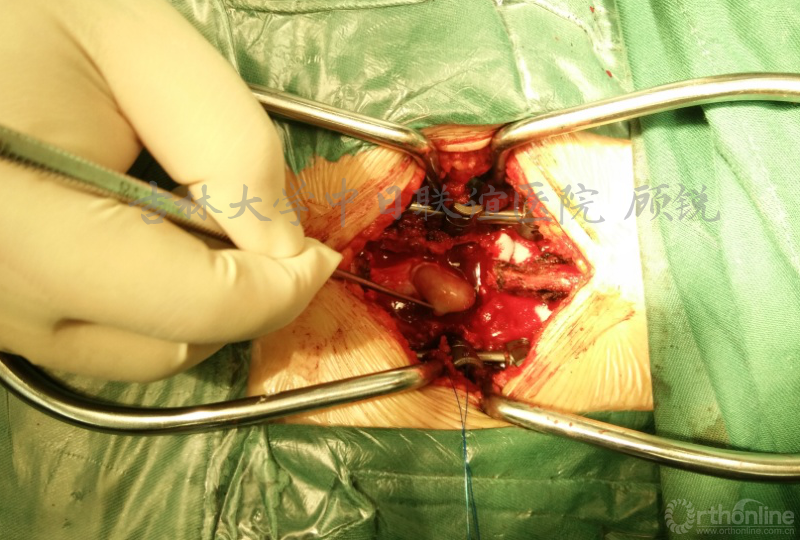

我们采取的手术方案是一期完成减压滑脱椎复位融合内固定+肿瘤摘除术。依据是:现患者椎管内占位已较大;滑脱复位后肿瘤压迫出现神经症状可能;腰椎滑脱手术后,后期因瘢痕等增加肿瘤摘除难度;本科已完成了大量的显微操作下IDEMT或马尾肿瘤摘除的病例,手术操作已较为娴熟)。

手术中注意事项:

1.在显微镜操作下摘除肿瘤;

2.硬膜缝合后硬膜补片贴覆;

3.术前静脉滴注2g头孢曲松钠预防感染。

术中所见: